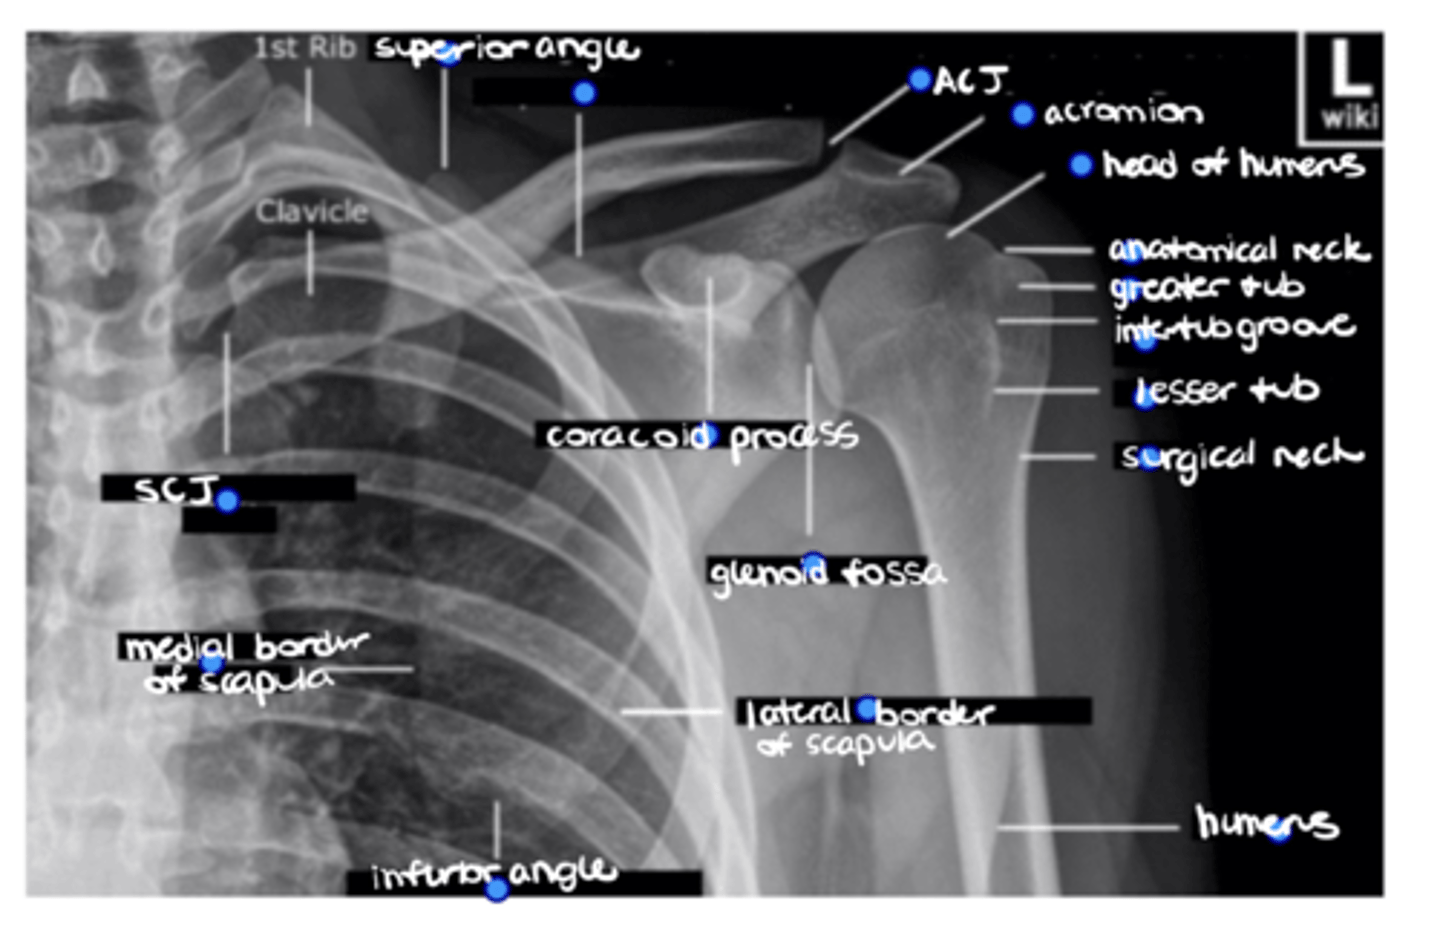

Superior angle of the scapula

ID the missing structure.

Superior border of the scapula

ACJ

Acromion

1. Head of humerus

2. Anatomical neck

3. Greater tuberosity

4. Intertubercular groove

5. Lesser tuberosity

6. Surgical neck

ID the 6 missing structures.

Shaft of the humerus

1. Coracoid process

2. Glenoid fossa

ID the 2 missing structures.

1. Lateral border of the scapula

2. Inferior angle of the scapula

3. Medial border of the scapula

ID the 3 missing structures.

SCJ